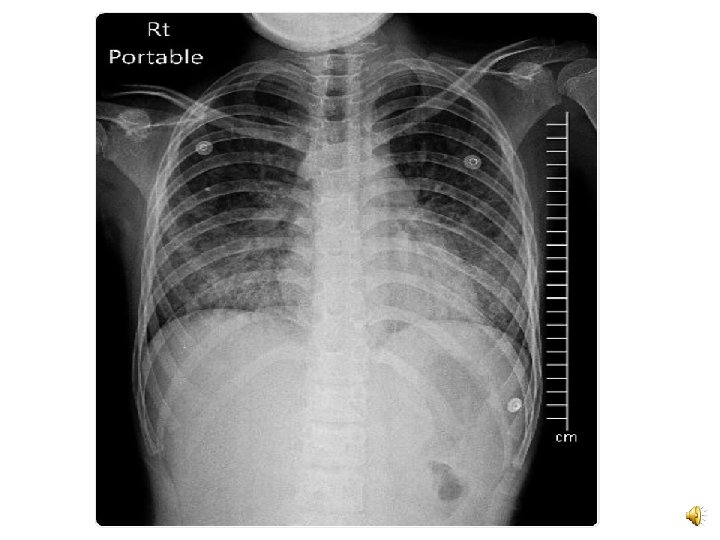

Respiratory distress Syndrome (RDS) • • Definition: Preterm neonate presenting with Tachypnea (R. R

Respiratory distress Syndrome (RDS) • • Definition: Preterm neonate presenting with Tachypnea (R. R > 60/ minute) Chest retractions Cyanosis CXR with reticulo-granular pattern and air bronchograms